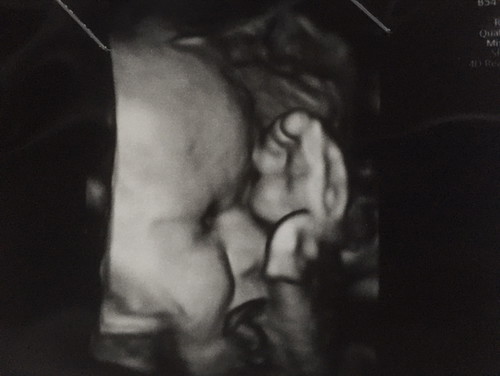

เจ้าอ้วงของแม่❤️❤️

36 week 2900 กรัม แม่ๆบ้านอื่นน้ำหนักน้องกี่กรัมแล้วค่ะ

แก้มหนูมาเต็มตั้งแต่อยู่ในท้องเลยอ่ะ 🤗🤗